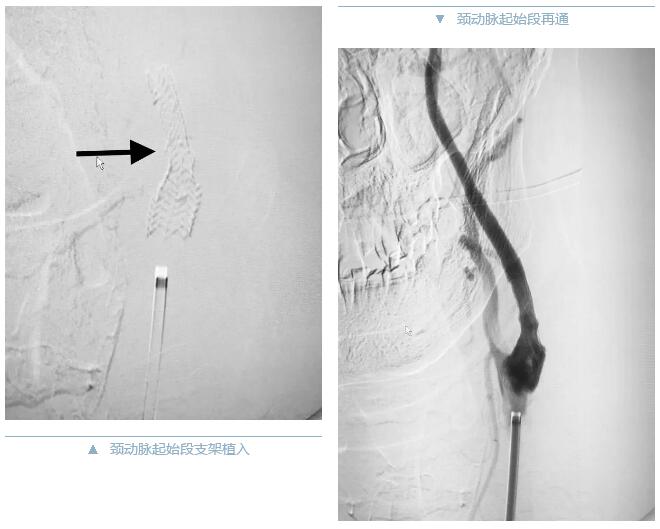

6点10分,患者被推入导管室手术间。脑卒中患者往往病情复杂多变,进展迅速,随时威胁生命。接到患者时,病人意识不清,躁动明显,配合手术困难。看到家属一双双无助却又满怀期待的眼神,和一声声“大夫您救救他吧!”神经内科副主任耿晓坤带领程哲和李凤海医生,在导管室护士和技师的配合下,毫不犹豫,立即组织实施手术。果然,造影结果证实:左侧颈内起始段闭塞,整个左侧大脑半球处于严重缺血状态,大量脑细胞濒临死亡!此时距患者发病已经5个小时……时间越长,越多的脑细胞就会发生不可挽回的缺血损伤!手术台上,患者的生命体征更是不容乐观,心率、血压不稳,舌后坠明显、呕吐,随时还有窒息的危险。耿主任顶着时间与病情危重的双重压力,手中细如发丝的介入导丝、导管,如灵蛇一般,精确快速地穿过了血栓,在团队医师的密切配合下将取栓支架送入闭塞病变处.....很快大量的血栓被从血管中顺利取出!再次造影,整个左侧大脑半球血流恢复!但随即又发现了新的问题,如果说血栓是行凶的主犯,那么刚开通的颈动脉严重的残留狭窄就是一个定时炸弹,“管道”不修好血栓将再次脱落并堵塞颅内的血管,再次危及生命。紧接着耿主任娴熟地将一枚支架置入到颈内动脉狭窄处,“管道”被彻底修复!大脑在重新得到新鲜血液灌溉后,患者奇迹般的恢复了,神志清楚,右上肢和右下肢肌力达到4级,已经接近正常!真的是太棒了!这样的结果,离不开潞河医院出色的脑卒中绿色通道,离不开神经介入团队紧密配合,离不开手术操作者精湛的技艺,离不开医护人员的精诚合作,不放弃,不抛弃,更离不开患者家属充分的信任!